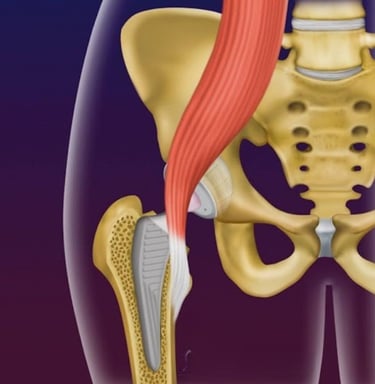

Tendinite de iliopsoas

É uma complicação infrequente, mas que causa dor na região da virilha após a colocação da prótese, principalmente ao se fazer flexão do quadril (movimento de puxar o quadril para cima).

Essa complicação pode ocorrer devido à proximidade do tendão do iliopsoas com a taça acetabular ou a cabeça da prótese, gerando um atrito constante entre o tendão e a prótese, levando à inflamação do tendão.

Imagem ilustrando o tendão do iliopsoas passando próximo à prótese de quadril, podendo causar tendinite do iliopsoas.